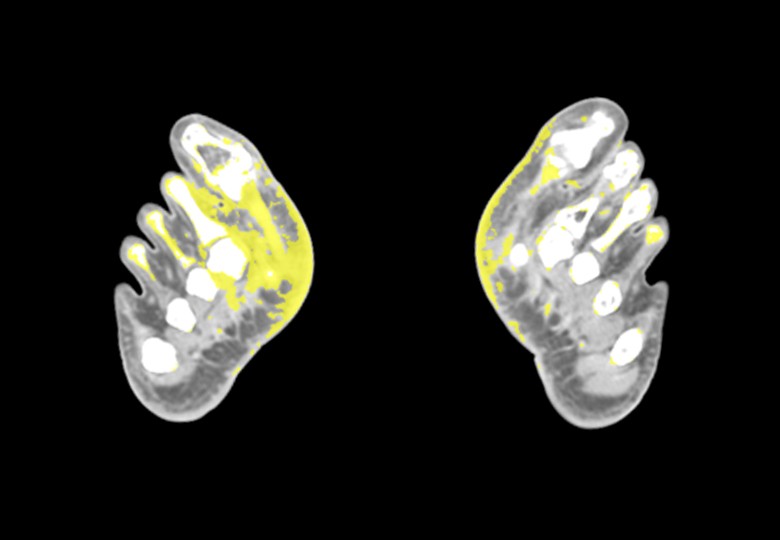

Spectral Scan